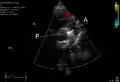

- An echocardiogram of a stented persisting ductus arteriosus: One can see the aortic arch and the stent leaving. The pulmonary artery is not seen.

- An echocardiogram of a coiled PDA: One can see the aortic arch, the pulmonary artery, and the coil between them.